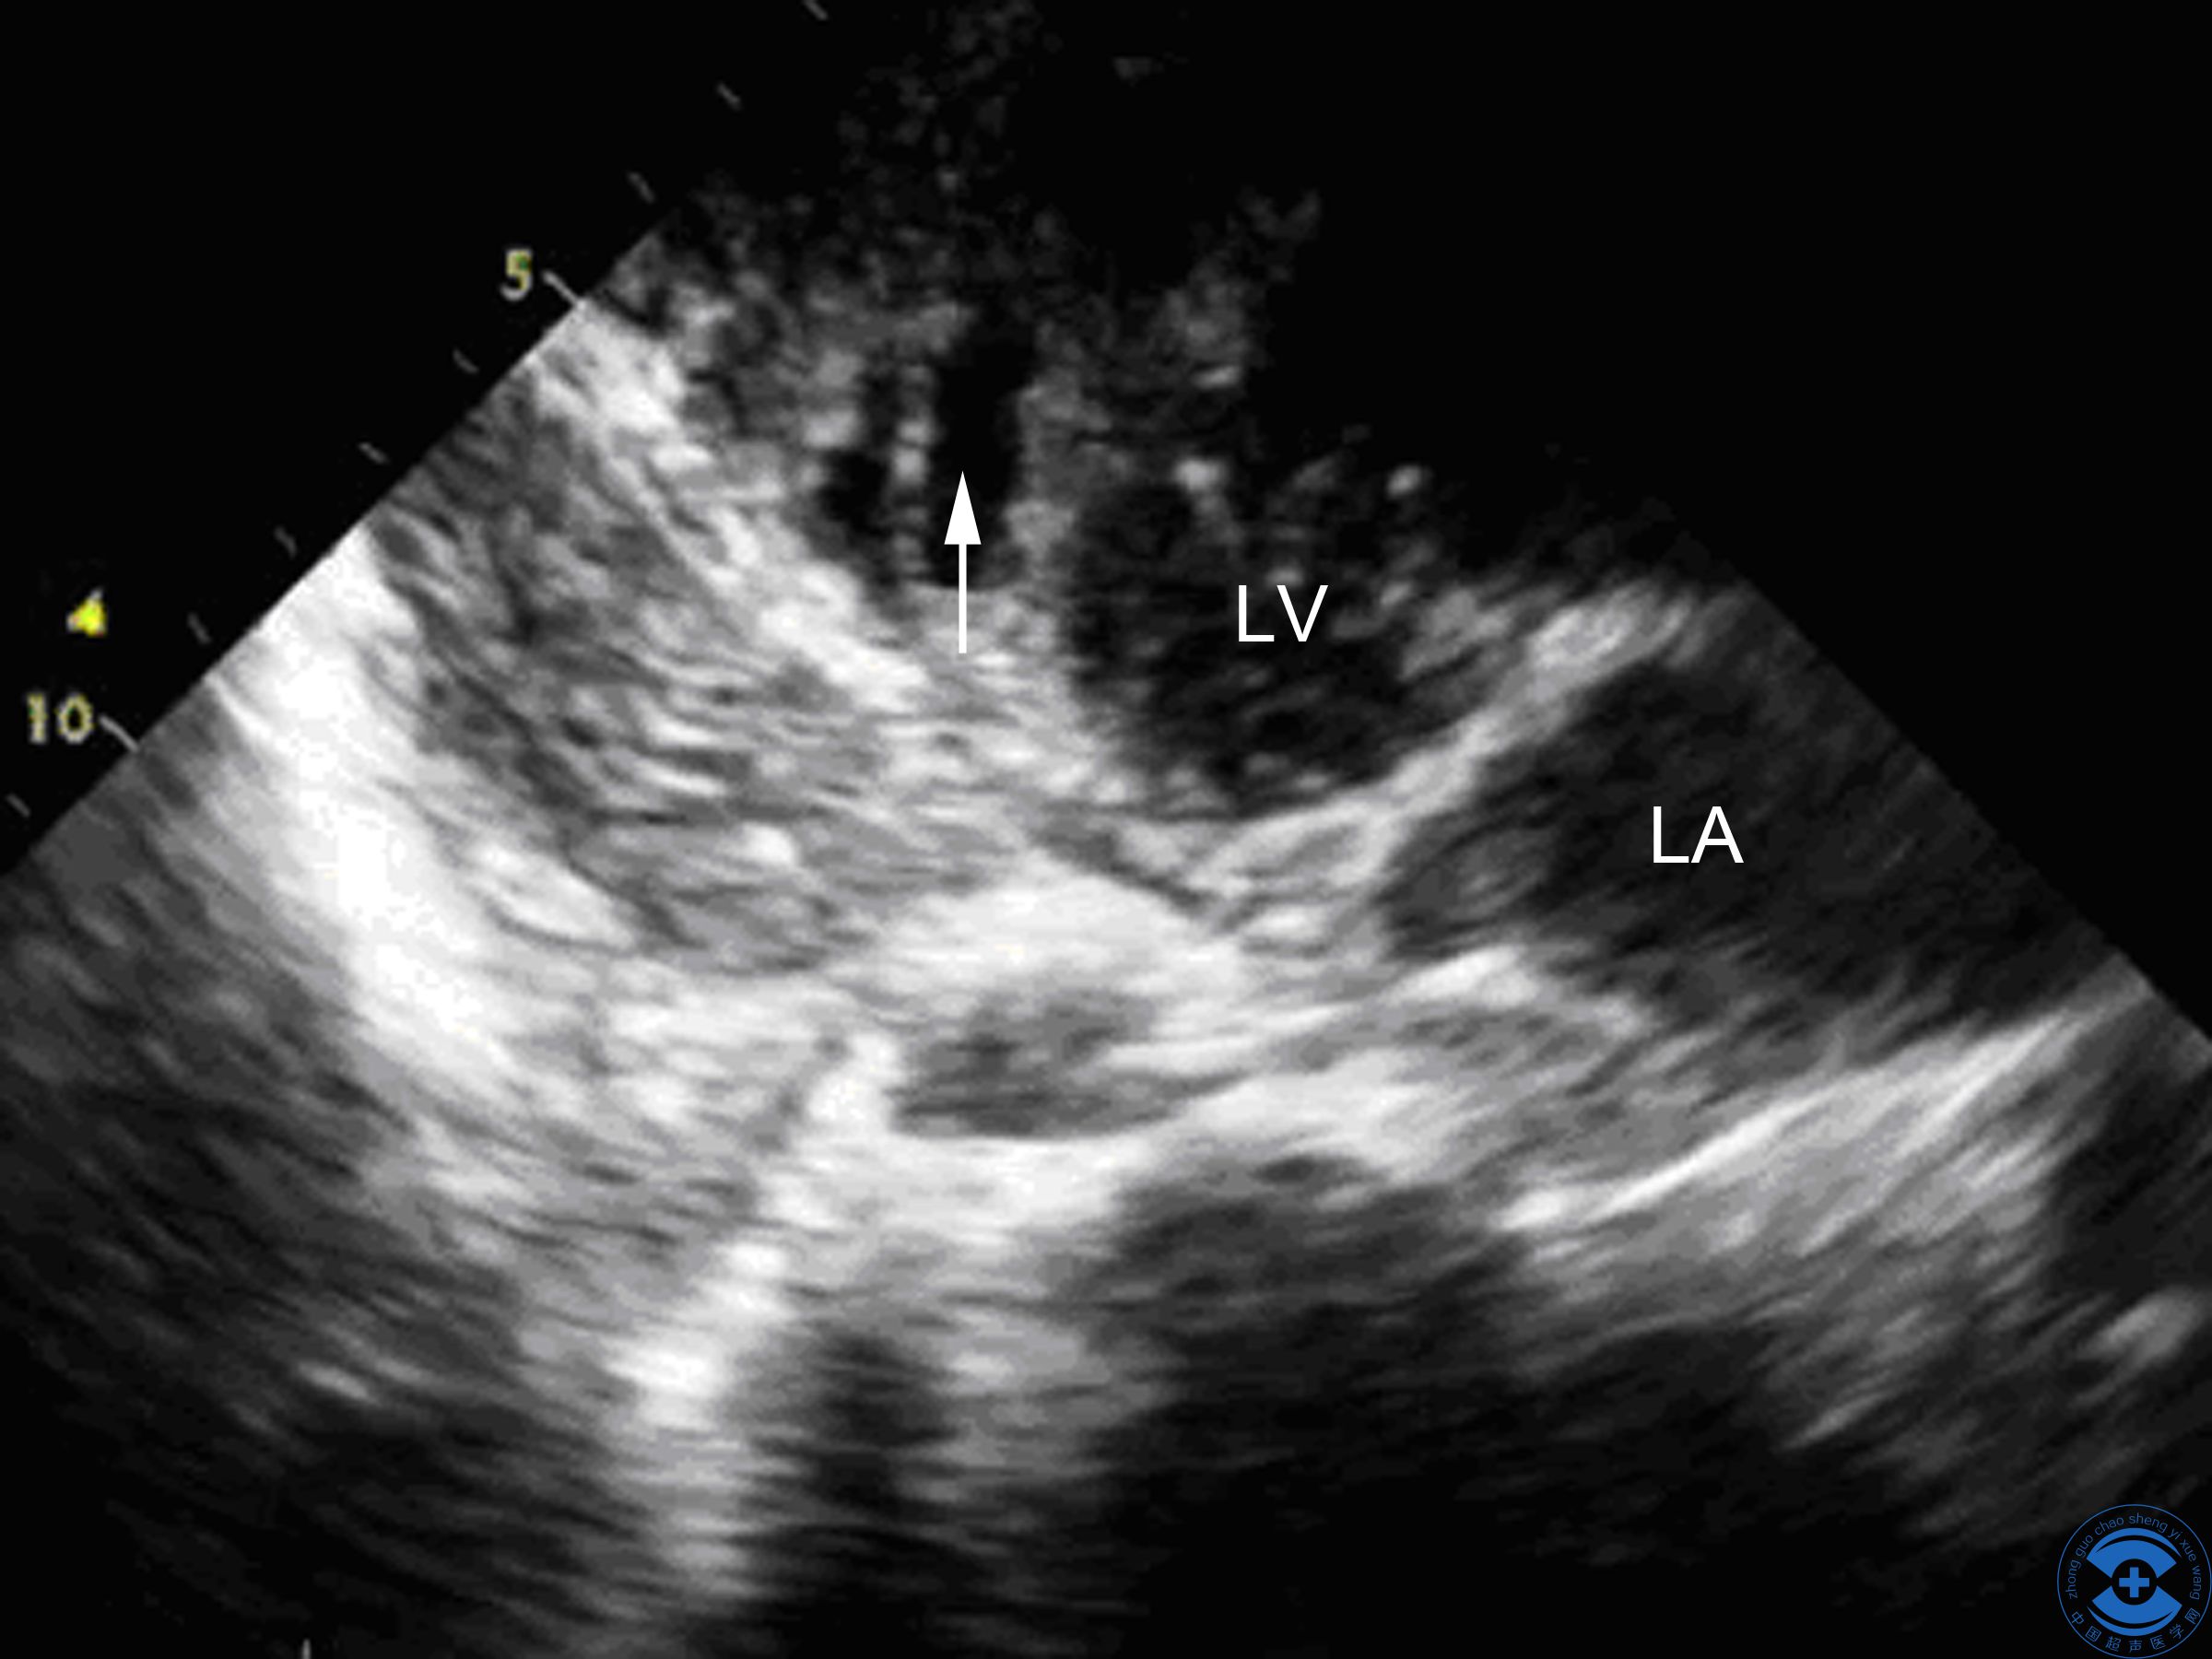

图1 后间隔心尖段回声中断:剑突下四腔心切面见后间隔心尖段回声中断,左室面中断约